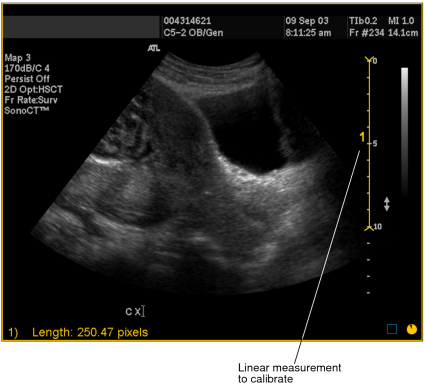

1. Select the image that you want to calibrate.

2. Draw the line whose length you will use to define the ratio of pixels-to-centimeters. You should draw this line on a scale or other element of the image whose length in centimeters is accurately known. To draw the line, click the Linear Measurement tool Linear Measurement tool.

3. Click at the starting point of your measurement and drag. Release the mouse button at the end of your measurement.

A numbered measurement line appears, and the corresponding length appears in the bottom left corner of the viewport. Notice that the length is displayed in pixels.

Linear measurement to calibrate